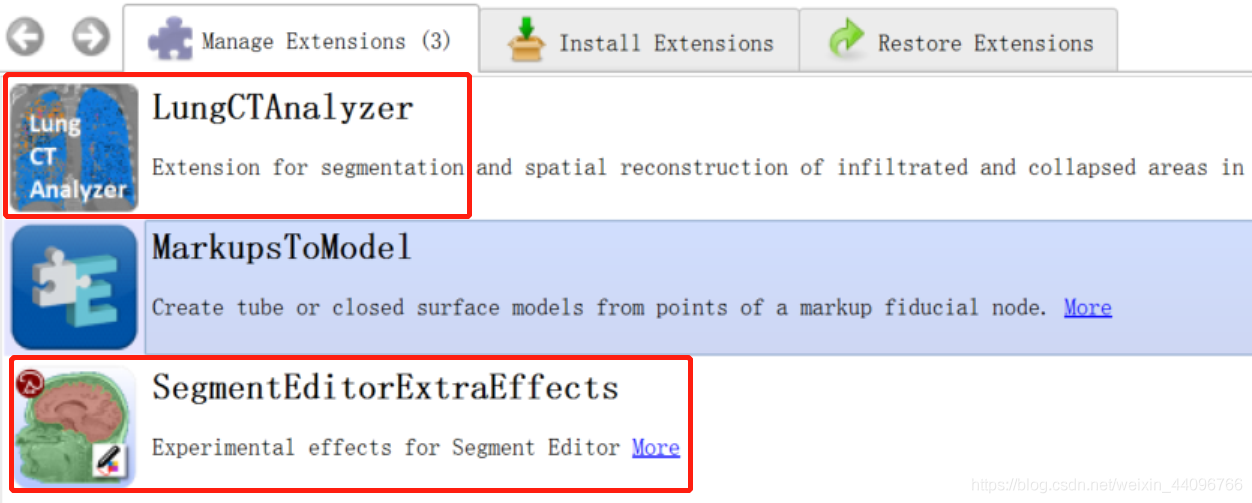

下载插件

在Install Extensions中查找下面框选的两个插件安装。

- LungCTAnalyzer

- SegmentEditorExtraEffects